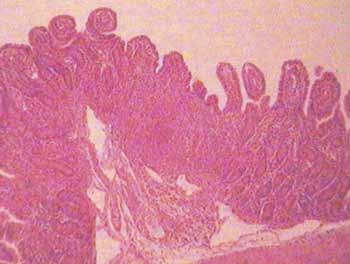

Both sheep and cattle farmers are being warned of the risks of coccidiosis in young stock this summer. Coccidiosis can affect calves and lambs. Although the main risk period for lambs is over by June most are affected at 4-8 weeks of age the Vecoxan Coccidiosis Survey 2009 found that cases were reported as late as 12 weeks of age, just as the lambs are approaching finishing. This can be significant economically, with weight gain adversely affected, even in the absence of obvious signs of disease, although there is often visible evidence of scouring.

The disease is less seasonal in calves, and it is commonly accepted that calves also tend to be affected at 4-8 weeks of age, but the survey found that the disease more frequently tends to peak at 12 weeks of age. The respondents to the survey indicated that dairy calves were most at risk, with 22% first affected at 12 weeks of age, but beef calves can also be affected at this later stage. For producers of spring born calves this might be a significant consideration this summer.Although coccidiosis tends to be a year round problem in calves, farmers should be on the look out for the disease 14-21 days after typical stressor events, such as castration, weaning and turn out on to pasture. The survey identified that a sudden bout of bad weather was the most common stressor.

Vecoxan can be given to calves and lambs at any age and does not interfere with the development of immunity. Nearly all animals will be exposed to the parasite but they suffer adverse effects if exposed to high parasite numbers or if they become more vulnerable due to lack of colostrum or other stress factors that impair immunity. Calves and lambs can be treated at an early age if there is a known pattern of disease on the farm or given timed treatment relating to risk factors most commonly 14 days after the risk to stop the 21-day parasite lifecycle in its tracks. Failure to treat early may provide some explanation for the late appearance of the disease in some cases.